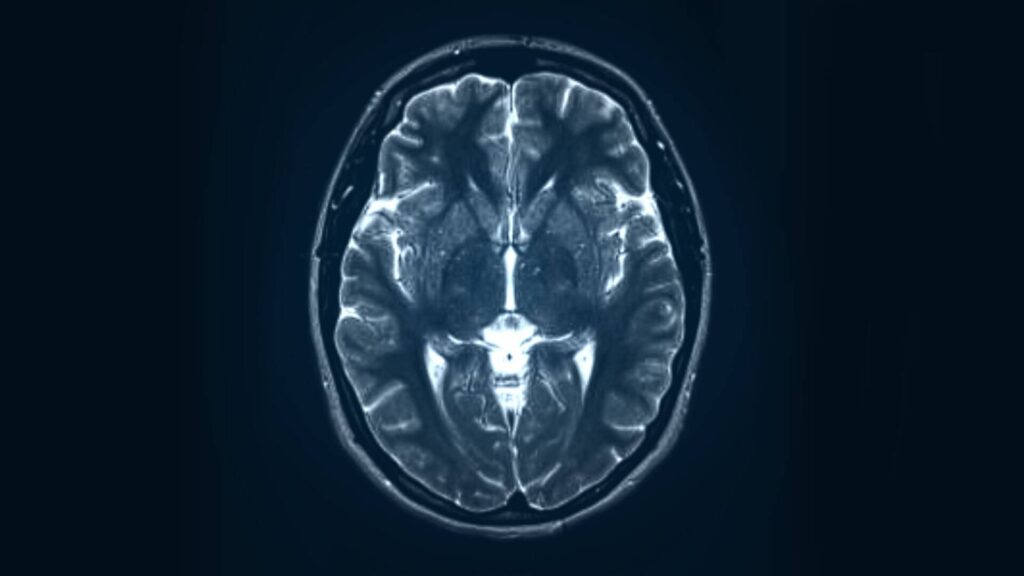

Científicos de la Universidad de Fudan de Shanghai, han conseguido que cuatro pacientes con parálisis por lesiones de médula recuperen el control de sus piernas a las 24 horas de una cirugía mínimamente invasiva. El secreto de estos revolucionarios resultados está en un nuevo implante cerebral desarrollado por el equipo que crea un puente o “bypass neuronal” que permite que el sistema nervioso del organismo se reconecte por sí mismo.

El nuevo chip del equipo chino se conecta al cerebro y a la médula espinal a la vez. Una vez colocado estimula directamente los nervios inactivos mediante un proceso que llaman “remodelación neuronal”, que permite que el sistema nervioso reconecte las vías propias del organismo.

La cirugía consiste en implantar un chip que integra la recogida de electroencefalogramas en el cráneo y la estimulación de la médula espinal en la columna vertebral. También lleva dos electrodos de aproximadamente 1 milímetro de diámetro que se implantan a ambos lados del cerebro y un electrodo de paleta que suministra estimulación eléctrica a las raíces nerviosas espinales que va implantado en la región lumbar.